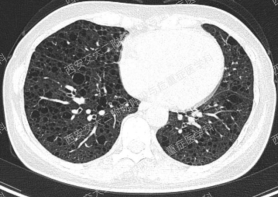

上图所示肺部囊性病变,双侧多发、大小不一,壁薄,形状不规则,呈圆形及扁平状为主,部分融合,分布多在纵隔胸膜下。入院后查血尿粪常规、肝肾功能电解质、凝血功能、血糖血脂心肌酶、BNP、肌钙蛋白正常;红细胞沉降率23mm/h,PCT、CRP正常;TB-spot阳性(阳性对照管反应水平123.49 pg/mL),TB-DNA、PPD试验、痰X-pert、痰涂片、痰培养均阴性;女性肿瘤标志物全套未见异常;结缔组织病相关指标:自身抗体ANA 1:100、CENP B阳性,CCP抗体25.1U/ml(正常参考值<17U/ml),ANCA、抗核抗体谱、体液免疫全套均阴性;血气分析大致正常,肺功能检查: FEV1占预计值78.2%,FEV1/FVC 69.55%,RV/TLC 49.62%,支气管舒张试验阴性,FeNO50 29.2ppb。